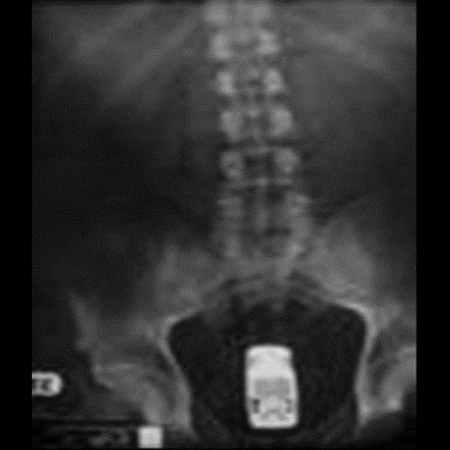

5. Βάζο με μαρμελάδα